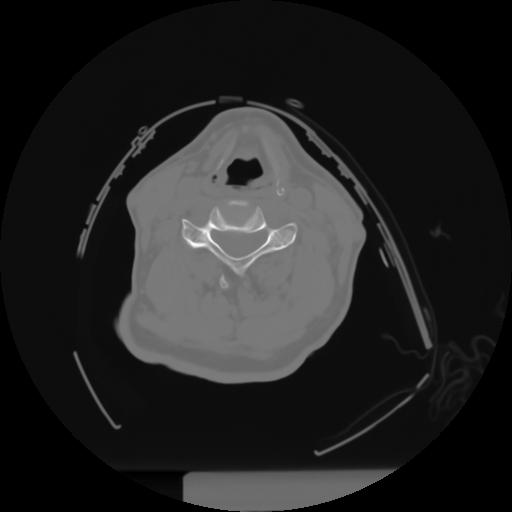

10 P.BLANDAS,,Axial,2.0,P.BLANDAS,,